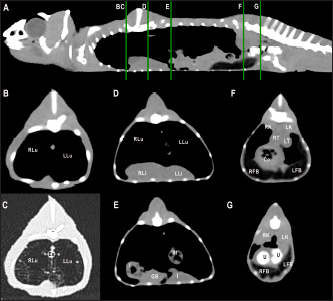

Fig. 5. Sagittal precontrast CT image displayed in soft tissue window (A) and selected corresponding transverse images represented as green line section, displayed in soft tissue (B, D–G) and lung window (C) at the level of the lungs, liver (D), gastrointestinal tract (E), fat bodies (F), and kidneys/urinary bladder (G) in a panther chameleon (F. pardalis). The right of the patient is on the left of the image. RLu, right lung; LLu, left lung; Es, esophagus; RLi, right liver lobe; LLi, left liver lobe; St, stomach; I, intestine; GB, gallbladder; RK, right kidney; LK, left kidney; RT, right testicle; LT, left testicle; Co, colon; RFB, right fat body; LFB, left fat body; U, urinary bladder with intraluminal content (urate salts) in the lumen visualized as multiple irregular mineral attenuating structures.

Fig. 6. Sagittal right paramedian precontrast CT image displayed in soft tissue window (A) and selected corresponding transverse images represented as green line section, displayed in soft tissue window at the level of the gallbladder (B), fat bodies (C), and kidneys/urinary bladder (D) in a veiled chameleon (C. calyptratus). H, heart; RLu, right lung; LLu, left lung; Es, esophagus; RLi, right liver lobe; LLi, left liver lobe; GB, gallbladder; RK, right kidney; LK, left kidney; RT, right testicle; LT, left testicle; I, intestine; RFB, right fat body; LFB, left fat body; U, urinary bladder; LF, left femur; RF, right femur; PB, pelvic bone.

Fig. 7. Sagittal right paramedian postcontrast CT image displayed in soft tissue window (A) and selected corresponding transverse images represented as green line section, displayed in soft tissue window, at the level of intestines (B), fat bodies and ovaries (C), and urinary bladder (D) in a female veiled chameleon (C. calyptratus). H, heart; GB, gallbladder; arrow, enhancement of the gallbladder; RLu, right lung; LLu, left lung; Ov, ovaric follicles; Co, colon; I, intestine; RFB, right fat body; LFB, left fat body; RAS, right air sac; LAS, left air sac; arrowhead, ovarian vessels; #, caudal vein; *, Li, liver; kidneys; U, urinary bladder; RF, right femur; LF, left femur; PB, pelvic bone.

Fig. 8. Sagittal precontrast CT image displayed in soft tissue window (A) and selected corresponding transverse images represented as green line section, displayed in soft tissue window at the level of the liver (B), ovaries (C), and kidneys/fat bodies (D) in a female panther chameleon (F. pardalis). E, eggs; RLi, right liver lobe; LLi, left liver lobe; ROv, right ovary; LOv, left ovary; RK, right kidney; LK, left kidney; LFB, left fat body.

Heart, liver, including caudal vena cava (CVC), hepatic vessels, and gallbladder, esophagus, stomach, intestines, cloaca, gonads, fat bodies, kidneys, and when distended, urinary bladder were identified in the CT images with the aid of the anatomical sections (Fig. 4). The spleen, pancreas, and adrenal glands could not be identified. Measurement values of the liver, testes, fat bodies, and kidneys observed in CT in veiled and panther chameleons are seen in Table 1.